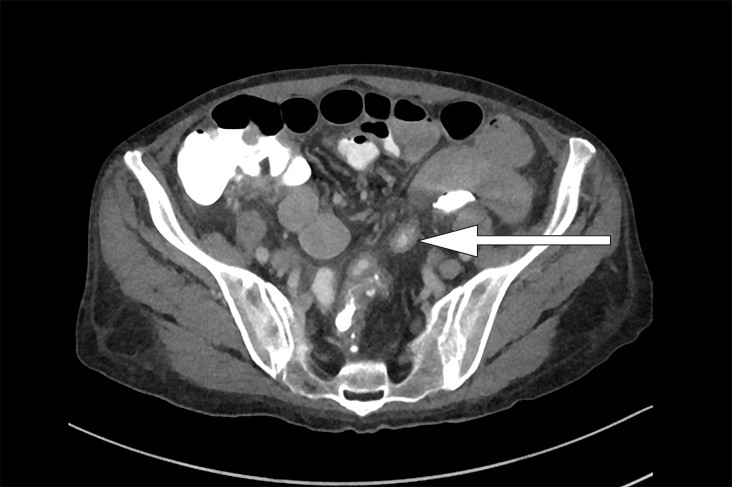

Én uke senere, i påvente av PET-undersøkelsen, ble pasienten reinnlagt grunnet diaré. Hun beskrev 6–8 vanntynne tømminger daglig uten synlig slim eller blod. Diareen var ledsaget av kvalme, men ikke oppkast eller magesmerter. Det var ingen relevant reise- eller medikamentanamnese, og ingen i omgivelsene hadde tilsvarende symptomer. Regranskning av CT-undersøkelsen fra forrige innleggelse viste, foruten mesenterial lymfadenopati, veggfortykkede tynntarmssegmenter (fig 1). Ved nærmere anamnese beskrev pasienten periodevis vanntynn/grøtaktig diaré de siste tre månedene samt 8 kg vekttap. Blodprøver viste INR 6,6 og reduksjon i serumalbumin fra 21,0 g/dl til 14,0 g/dl.

Konstellasjonen av migrerende leddsmerter og synovitter over flere år uten utvikling av radiologiske artrittforandringer, kombinert med intermitterende diaré og proteintapende enteropati gjorde at vi mistenkte Whipples sykdom, en sjelden infeksjonssykdom forårsaket av den grampositive bakterien Tropheryma whipplei. Pasienten ble henvist til gastroskopi og kapselendoskopi av tynntarm som viste betydelig inflammasjon med erosjoner, hemoragiske slimhinner og diffus lymfangiektasi (fig 2) (fig 3). Duodenalbiopsier viste breddeøkte totter og akkumulering av skummakrofager med periodisk syre-Schiff (PAS) diastasepositive granulære inklusjoner i cytoplasma (fig 4) (fig 5). Både de makroskopiske og histopatologiske funnene var godt forenlig med Whipples sykdom. PCR utført etter DNA-ekstraksjon fra parafininnstøpt tarmbiopsi var positiv for T. whipplei for to separate målgener (varmesjokkprotein og 16S rRNA). Sekvensering av 16S rDNA PCR-produktet bekreftet T. whipplei. Pasientens ikke-destruktive seronegative artritt, diaré, malabsorpsjon og utmattelse ble antatt å representere manifestasjoner av Whipples sykdom. Iskemiske slag og lungeembolier er beskrevet hos pasienter med Whipples sykdom, og sykdommen representerte en plausibel årsak til pasientens hittil uforklarlige trombosetendens (1),( 2).

Klassisk Whipples sykdom diagnostiseres på bakgrunn av øvre endoskopi, duodenalbiopsier og PCR-undersøkelse. Gastroskopi kan vise ødematøse slimhinner med erosjoner og lymfangiektasi. Lymfangiektasien skyldes akkumulering av makrofager i lymfekarene, med resulterende lymfestase. Allikevel er det viktig å være klar over at de fleste pasientene har makroskopisk normal tynntarmsslimhinne, så biopsier anbefales selv ved upåfallende gastroskopi (5). Multiple biopsier øker sensitiviteten (6). Kapselendoskopi av tynntarm kan brukes for å kartlegge sykdomsutbredelsen. Mikroskopering av duodenalbiopsi viser akkumulering av skummakrofager med PAS-positive intracellulære inklusjoner. Det PAS-diastase-positive materialet svarer til bakteriekapselen som inneholder mykopolysakkarider. Andre årsaker til PAS-positive makrofagansamlinger i tynntarm er blant annet mykobakterieinfeksjon, avleiringssykdommer og langerhanscelle-histiocytose. Disse differensialdiagnosene kan avkreftes med tilleggsundersøkelser.